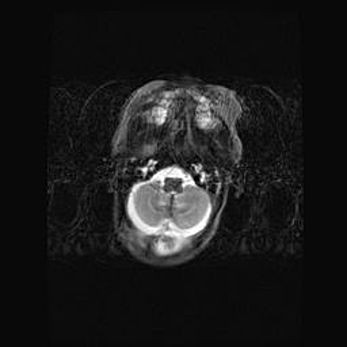

Сообщающаяся гидроцефалия. Кистозная энцефаломаляция головного мозга.

Возраст: 3 месяца 4 дня

Вес: 3100 г

Пол: женский

Окружность головы: 34 см

Срок гестации: 31 неделя

Кистозная энцефаломаляция головного мозга - одна из форм поражения головного мозга в детском возрасте. Характеризуется возникновением множественных и распространённых кист в коре, белом веществе и подкорковых образованиях головного мозга у плодов, новорождённых и детей раннего возраста. Развитие кистозной энцефаломаляции связано с внутриутробной асфиксией и гипотонией, родовой травмой, тромбозом синусов, пороками развития сосудов, инфекциями, сепсисом и другими причинами. Наиболее значимые инфекционные агенты: вирусы простого герпеса, цитомегалии, краснухи, токсоплазмы, энтеробактерии, золотистый стафилококк и другие.